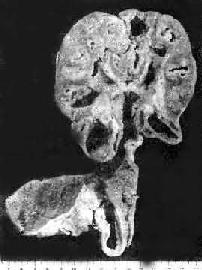

1.肾结核病 最常见于20~40岁。男性多于女性。多为单侧性、双侧性肾结核的发病率约为10%。病变开始于肾皮、髓质交界处或乳头体内。初为局灶性结核病变,病变继续扩大发展则发生干酪样坏死,破坏肾乳头而溃破入肾盂,成为结核性空洞。随着病变在肾内扩大蔓延,形成多数结核空洞,最后可使肾仅剩一空壳(图18-15)。由于液化的干酪样坏死物可随尿液下行,常使输尿管及膀胱感染。输尿管粘膜可发生溃疡和结核性肉芽组织形成,使管壁增厚、管腔狭窄,甚至阻塞,结果常引起肾盂积水或积脓。膀胱三角区往往最先受累,形成溃疡,以后可侵及整个膀胱,可引起膀胱壁纤维化,使膀胱容积缩小(膀胱挛缩)。膀胱的溃疡和纤维组织增生如影响到对侧的输尿管口,可使管口狭窄或失去正常的括约肌功能(关闭不全),造成对侧健肾引流不畅,最终可引起肾盂积水。结核菌也可逆行感染对侧肾。

肾结核及输尿管结核

图18-15 肾结核及输尿管结核

肾实质内多数干酪样坏死灶及空洞形成;输尿管壁增厚,粘膜有多数结核结节及浅表溃疡形成